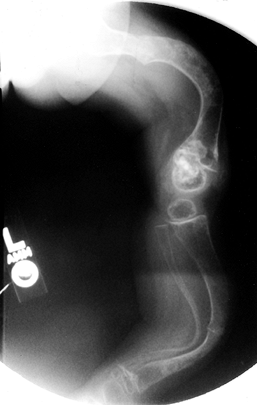

well. Fractures may be seen throughout the skeletal system. Coxa vara

is a common sequela of femoral neck fracture. Protrusio acetabuli can

develop. Wormian bones are seen on skull radiographs. The vertebrae may be biconcave, and compression fractures may be present (Fig. 180.9).

The long bones are thin and osteopenic. The femur may have a

“concertina” appearance, that is, a crumpled shape due to multiple

fractures. There is widening of the metaphyses, and growth arrests may

occur. Irregular calcifications may extend into the metaphysis, a

condition referred to as “popcorn epiphysis” (Fig. 180.10).

Figure 180.9. Flattened vertebral bodies throughout the spine of a 1-year-old boy with severe osteogenesis imperfecta.